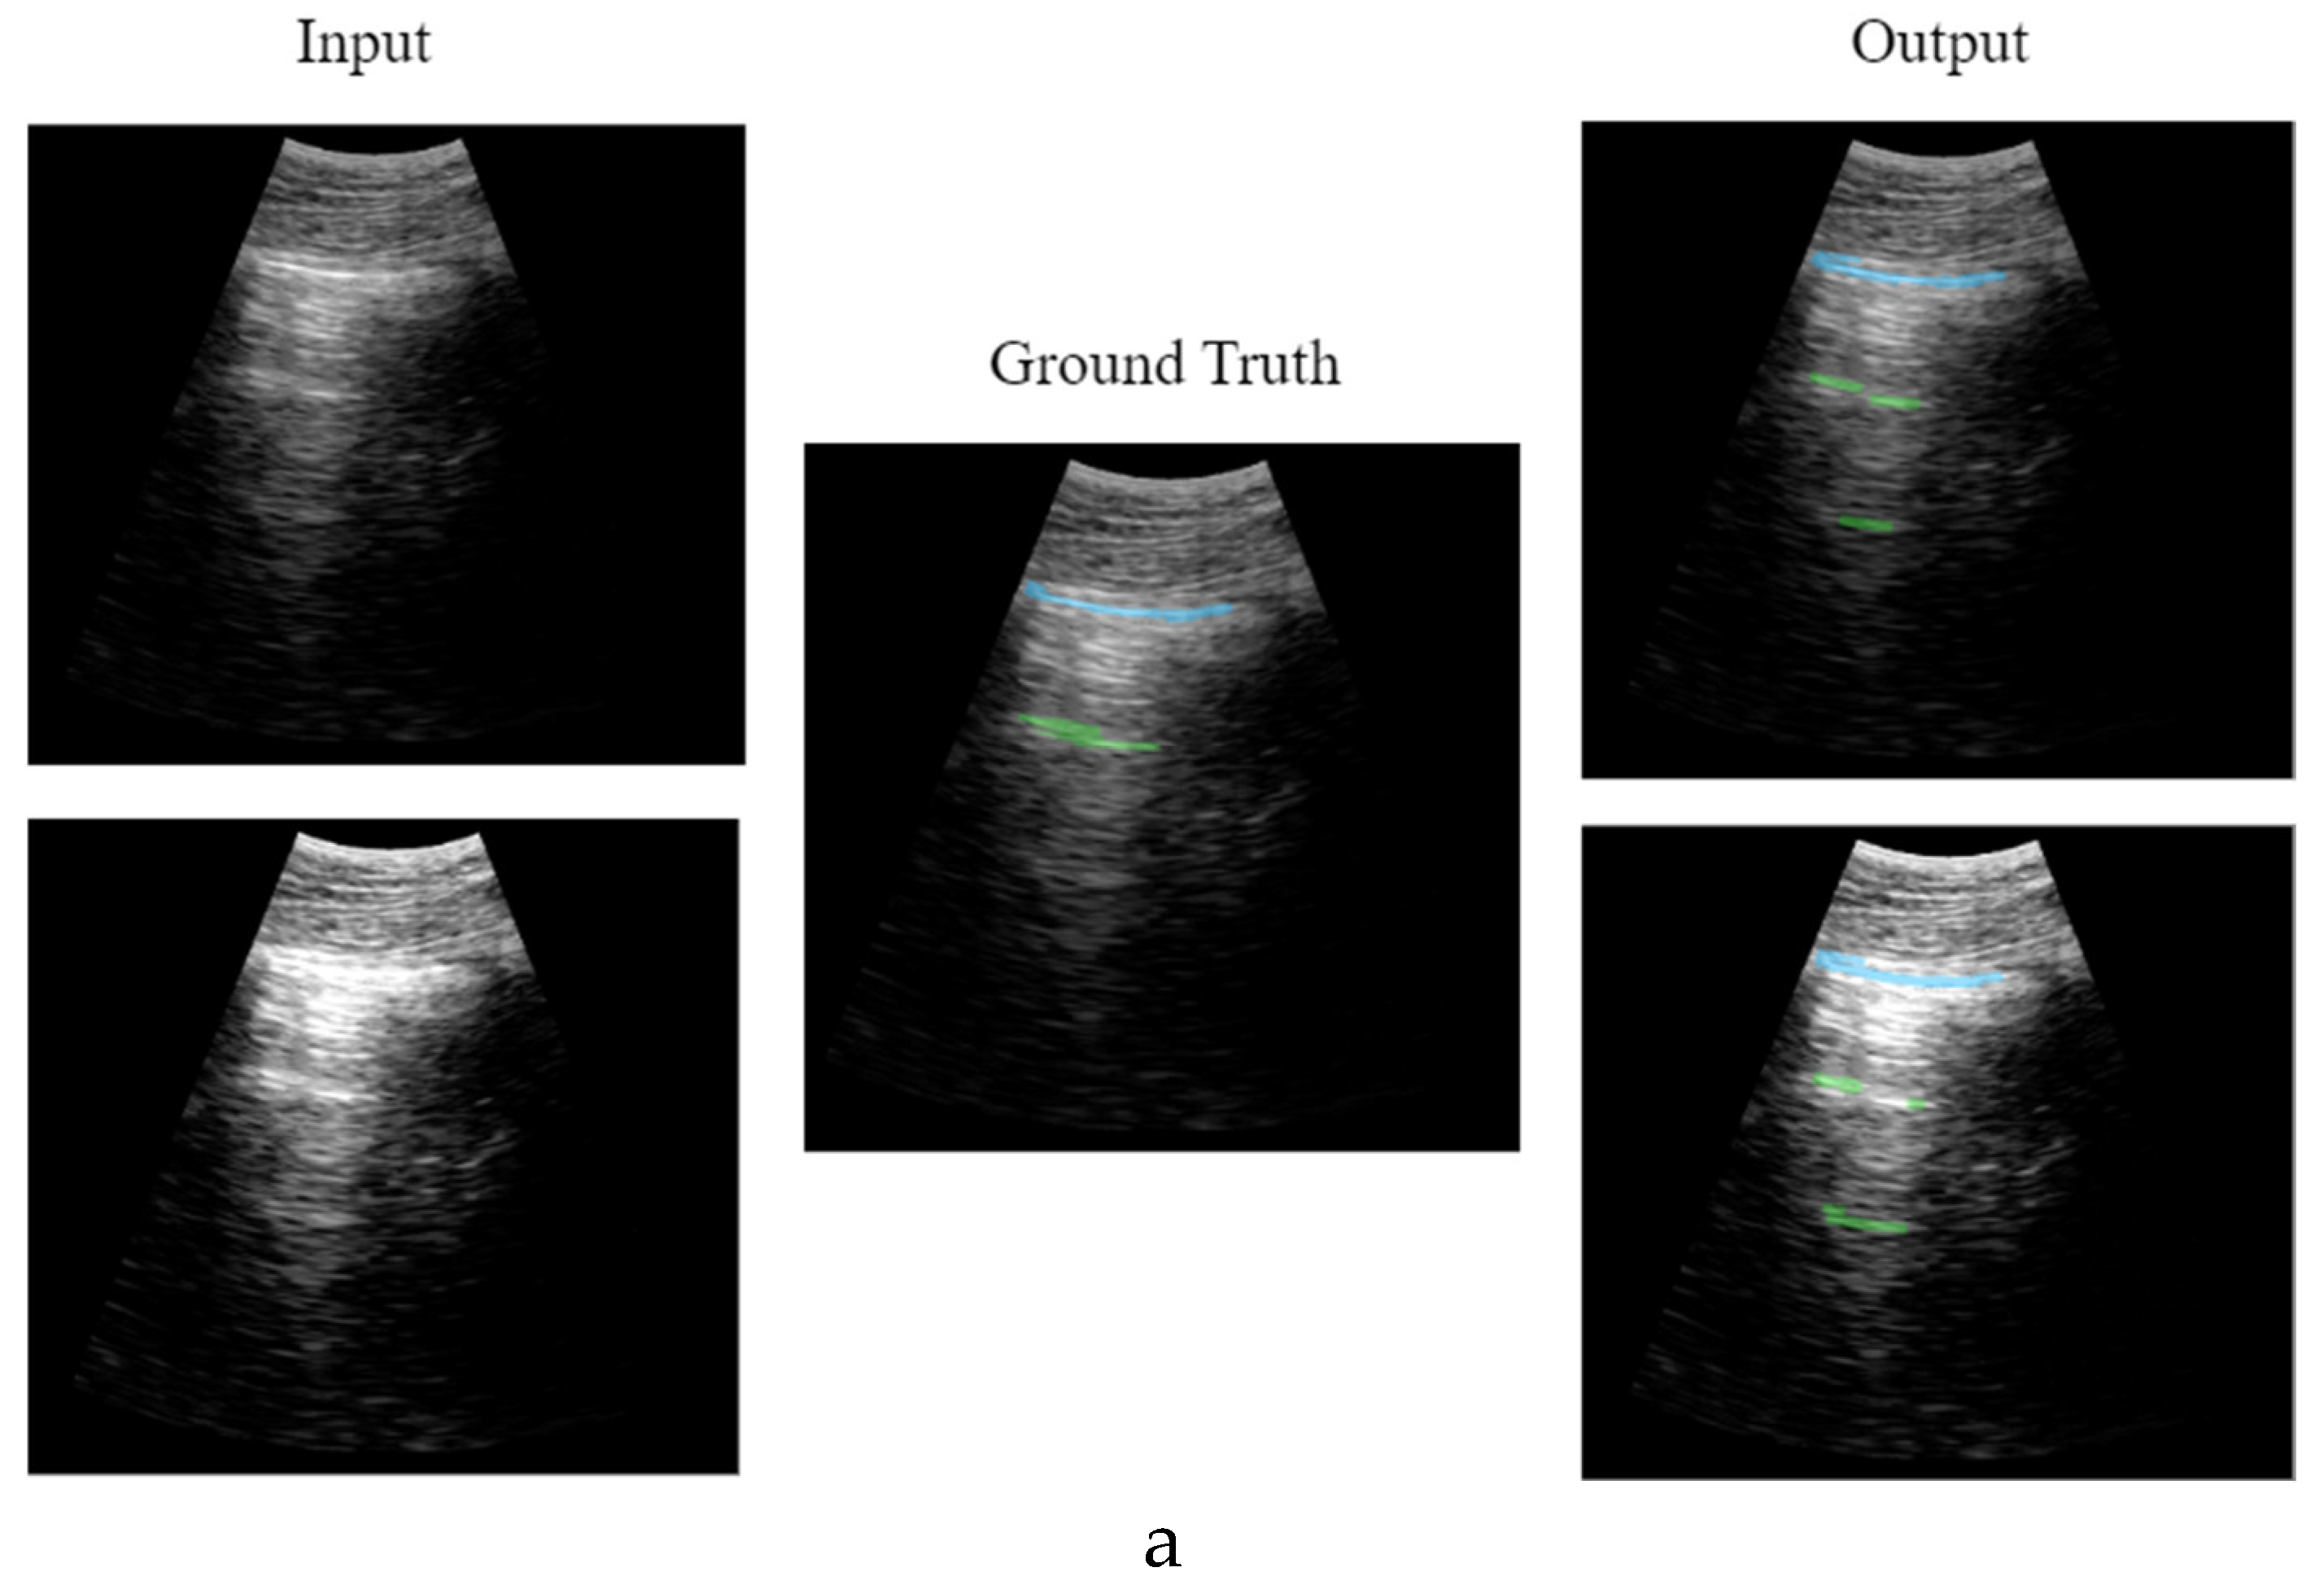

2.4.2. CNN Output

The output of the network proposed in this work, instead of a multiclass segmentation, adopts a multi-output binary segmentation approach, with each output dedicated to a distinct artifact: Pleura, A-line, B-line and consolidation. This strategy ensures a more accurate delineation of boundaries unique to each artifact, avoiding the risk of predictions blending or obscuring one another within the image, and facilitating identification and classification of multiple artifacts simultaneously.

Consequently, the network will output 4 binary masks, with a size of 128 x 256 pixels each, corresponding to each artifact studied in this work.

2.9.2. Model Prediction

Only if the pre-processing criteria have been met, the inference of the artificial intelligence model is performed. As explained in previous sections the inference is conducted frame by frame as soon as the real-time process is free, and then 4 different binary segmentation mask are obtained: pleura, consolidation, a-lines and b-lines.